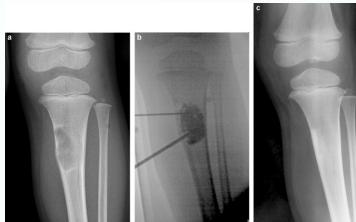

Non-ossifying fibroma …Fibrous cortical defect

Simple Bone Cyst

- Solitary – unicameral

- Children

- Metaphysis:

- Prox. Humerus and Femur

- Not a tumor:

- Not seen in adults

- Heals spontaneously

- Pathological fracture / or incidental

- Aspirate is clear straw-colored

Treatment

- Small, reducing in size:

- Leave alone

- Increasing in size, active:

- Moderate trial of bone marrow injection

- Large (risk of fracture) Curettage & grafting

- Pathological fracture:

- Treat fracture

- Cyst might heal

- Recurrent / injection failed:

- Surgical curettage and bone grafting